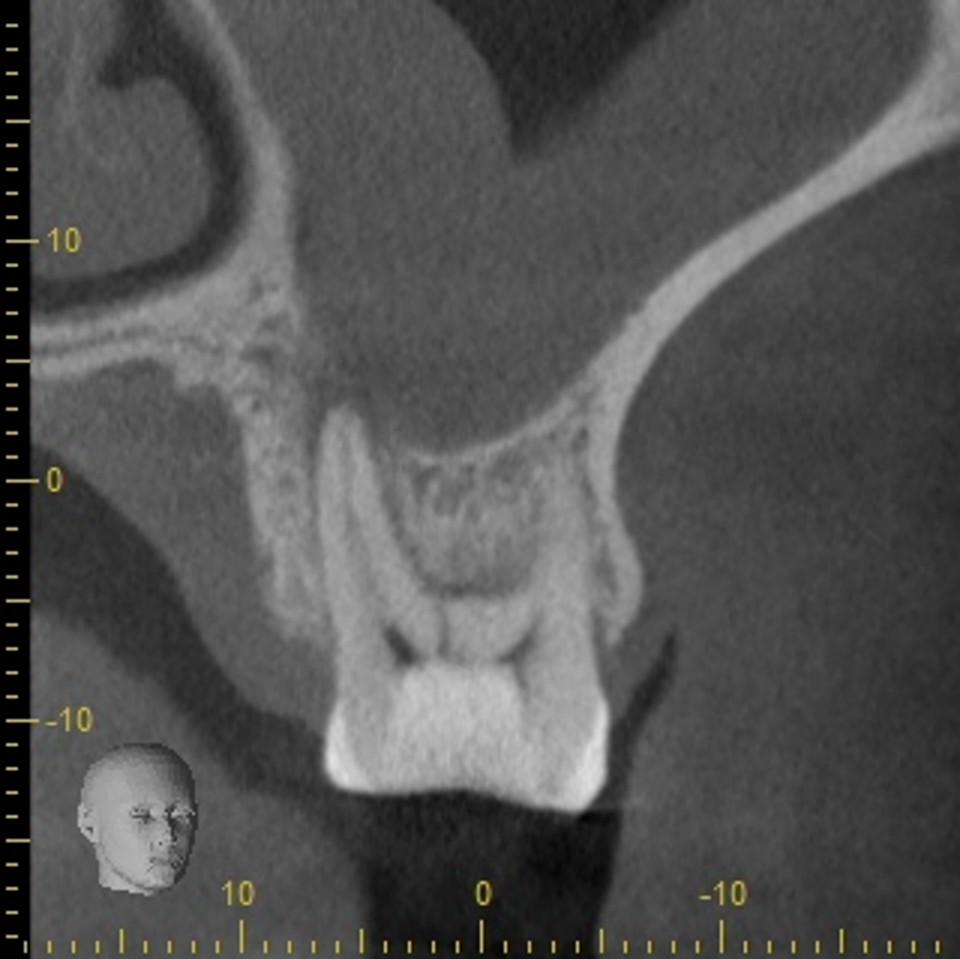

このように健康な歯が真っ二つに割れることはめったにないのですが、こうなると神経に触る様な強い痛みが出ますし、CTスキャンをとると上顎洞炎にもなっていました。

CTスキャンで確認してみても上顎洞炎もきれいに治っていることが分かります。